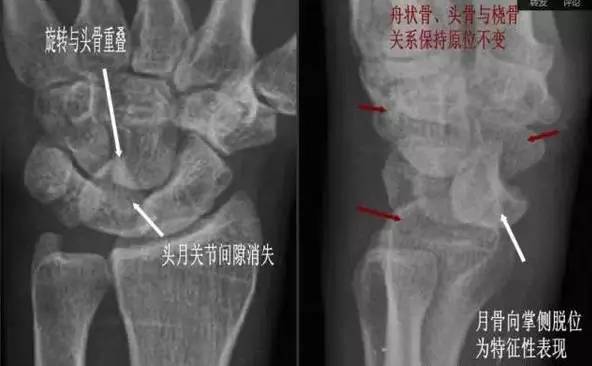

(1)月骨脱位:正位片示月骨由四边形变成三角形或橘瓣状,并向尺侧移位。侧位月骨前移、旋转,窝状关节前空虚。

月骨脱位影像特点

(3)月骨周围脱位:表现为腕关节缩短,头骨与桡骨距离变近,头骨、钩骨与月骨部分重叠,月骨形态及位置基本正常。

月骨周围脱位影像特点